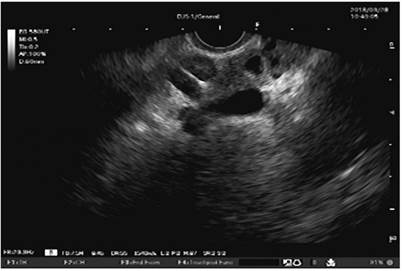

Calcifications or calculi in secondary branches (Figure 1)

Figure 1 Calculi in the parenchyma of the pancreas and branches seen by Fujinon’s linear endosonography (image edited by the Union of Surgeons SAS, Lázaro Arango).